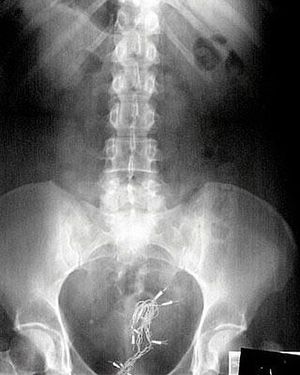

This patient may have taken holiday decorating to a new level....a level I would not ever want to be at. Remember folks Christmas decorations are for the tree Any takers on what we see here!?? Comment below πŸ‘‡πŸΌ Photo by @drcellini

Christmas light???

This patient is lit